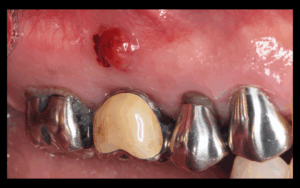

歯周外科治療